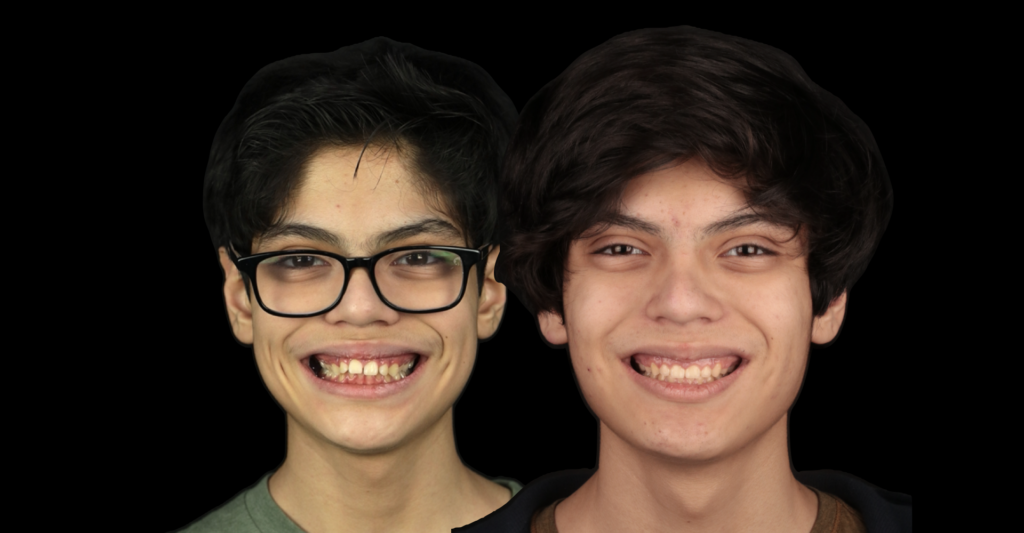

Caso clínico:

Les presentamos un caso clínico atendido por el Dr Quijada, el paciente presentaba una

deformidad dentofacial Clase II división I; este caso fue particularmente retador ya que ademas de corregir la función y estética dental, el doctor tenia la consigna de mejorar la estética facial. En esta ocasión realizamos la extracción de dos piezas premolares en la arcada maxilar superior y nos apoyamos de dos microimplantes dentales en la misma zona para poder obtener un máximo anclaje óseo para poder retraer el sector anterior maxilar que se encontraba protruido, es decir hacia adelante. Al final obtuvimos una transformación

impresionante en el aspecto funcional y estético. Ademas el paciente quedo satisfecho con la transformación de su dentadura.